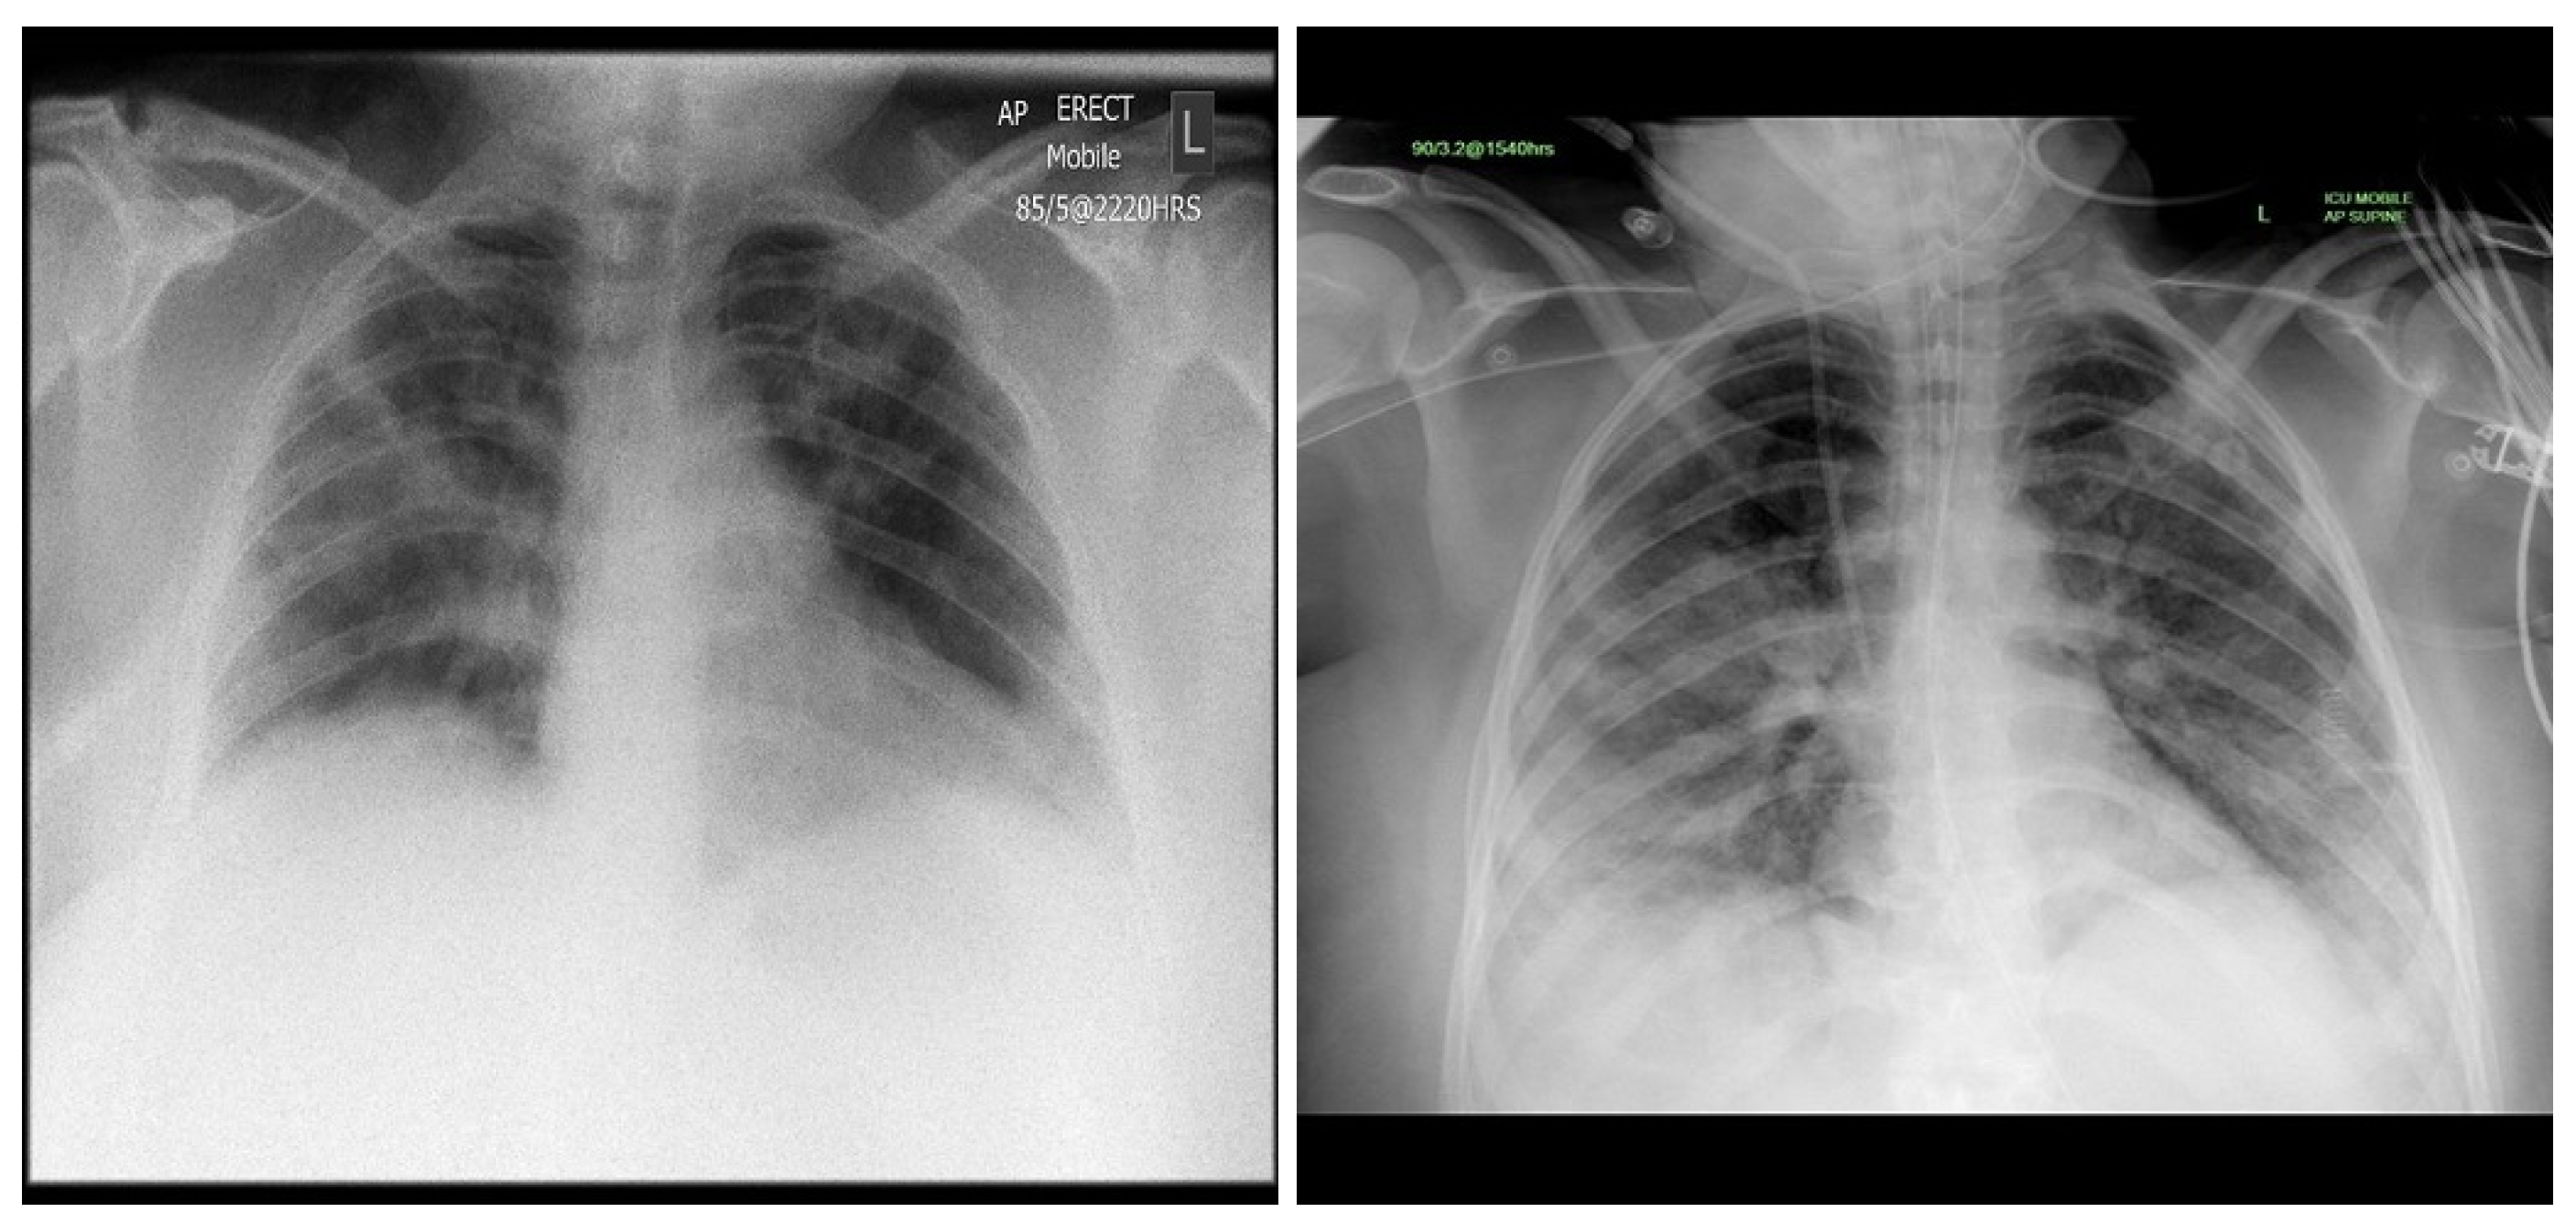

Deep Learning Model

4. Experimental Results

4.4. Results

4.5. Explainability